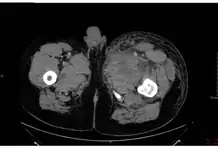

In December 2009, an outbreak of anthrax occurred among injecting heroin users in the Glasgow and Stirling areas of Scotland, resulting in 14 deaths.[23] The source of the anthrax is believed to have been dilution of the heroin with bone meal in Afghanistan.[24] Injected anthrax may have symptoms similar to cutaneous anthrax, with the exception of black areas,[25] and may also cause infection deep into the muscle and spread faster. [26] This can cause it to be harder to recognise and treat.